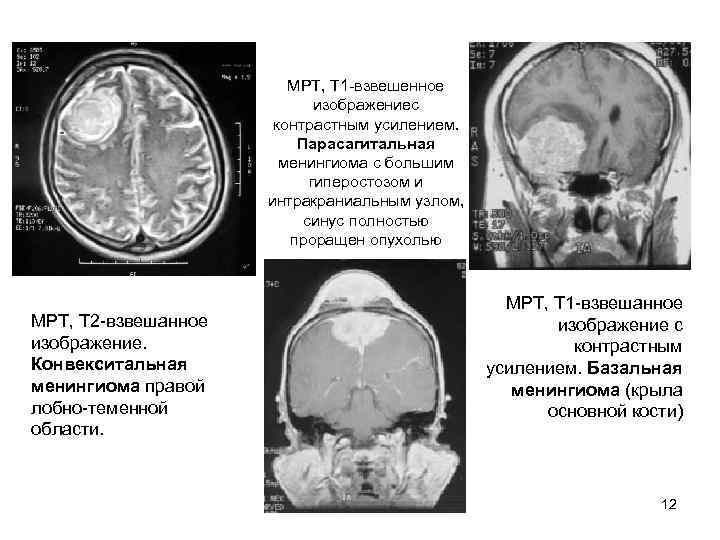

МРТ, Т 1 взвешенное изображениес контрастным усилением. Парасагитальная менингиома с большим гиперостозом и интракраниальным узлом, синус полностью проращен опухолью МРТ, Т 1 взвешанное МРТ, Т 2 взвешанное изображение с изображение. контрастным Конвекситальная усилением. Базальная менингиома правой менингиома (крыла лобно теменной основной кости) области. 12